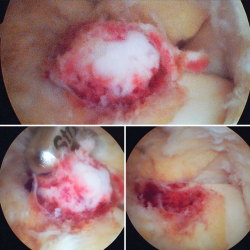

Figura 4. Mediante los portales artroscópicos anteriores habituales (anteromedial y anterolateral) se observa a nivel del cuello del astrágalo anterointerno la característica tumoración de color rojo cereza, que se desbridó con sinoviotomo.

Se visualizó la cúpula astragalina y se observó a nivel del cuello del astrágalo anterointerno una tumoración rojiza con intensa reacción sinovial; se desbridó mediante un sinoviotomo de 4,5 mm (Stryker®, Kalamazoo, Michigan) (Figura 4), tras lo cual se comprobó la inestabilidad de la lesión que se desprendió en bloque (Figura 5), remitiéndose a estudio anatomopatológico.